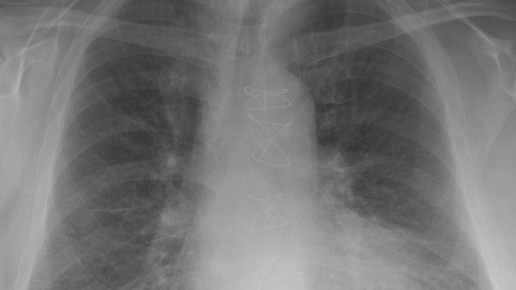

Feinstaub besteht aus einem komplexen Gemisch fester und flüssiger Partikel und wird abhängig von deren Größe in unterschiedliche Fraktionen eingeteilt. Unterschieden werden PM10 mit einem maximalen Durchmesser von 10 µm, PM2,5 sowie ultrafeine Partikel mit einem Durchmesser von weniger als 0,1 µm. Entscheidend für die gesundheitliche Wirkung von Feinstaub ist die Partikelgröße: Je kleiner die Staubpartikel sind, desto größer ist das Risiko, zu erkranken, da sie aufgrund ihrer Größe tiefer in die Atemwege eindringen können als größere. Dadurch gelangen sie in Bereiche, aus denen sie beim Ausatmen nicht wieder ausgeschieden werden.

PM10 kann beim Menschen in die Nasenhöhle, PM2,5 bis in die Bronchien und Lungenbläschen und ultrafeine Partikel bis in das Lungengewebe und sogar in den Blutkreislauf eindringen. Je nach Größe und Eindringtiefe der Teilchen unterscheiden sich die gesundheitlichen Auswirkungen. Sie reichen von Schleimhautreizungen bis zu verstärkter Plaquebildung in den Blutgefäßen, einer erhöhten Thromboseneigung oder Veränderungen der Regulierungsfunktion des vegetativen Nervensystems (Herzfrequenzvariabilität).